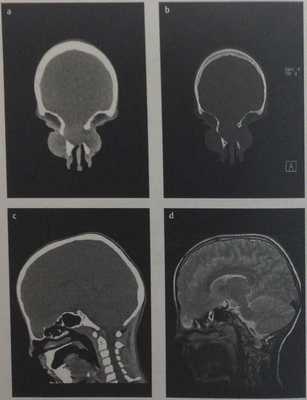

![Снимки МРТ и КТ. Энцефалоцеле основания черепа]()

Лобно-базальное менингоэнцефалоцеле. КТ: дефект кости (a,b), протрузия тканей головного мозга в параназальные мягкие ткани лица (с). МРТ, Т2-взвешенное изображение (d): четко дифференцируются вещество и оболочки головного мозга.